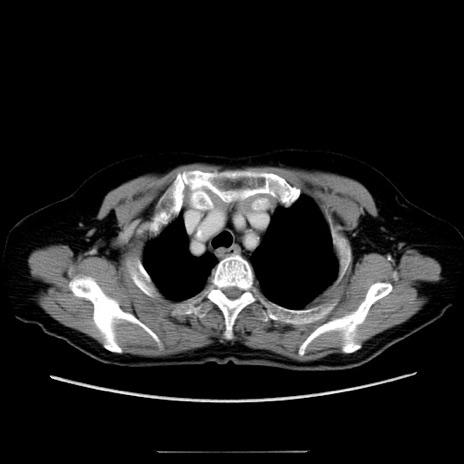

症例5(横断像)

【症例】70歳代女性

【主訴】お腹が張る

【現病歴】1週間くらい前から腹部膨満の自覚あり。昨日夜から増悪したため、本日救急外来受診。

【身体所見】意識清明、BT 36.5℃、BP 165/106mmHg、HR 80bpm、SpO2 98%、腹部:膨満、軟、自発痛・圧痛なし、触診にて不快感あり、腸蠕動音:減弱

【データ】WBC 12600、CRP 1.04